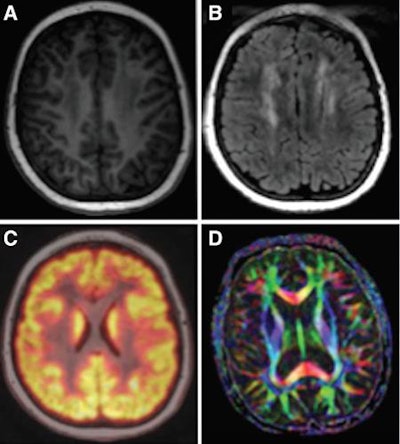

The brain MRI protocol included T2-weighted fluid-attenuated inversion-recovery (FLAIR) sequences. For cardiac imaging, cardiac short-axis steady-state free-precession cine sequences were performed to detect signs of anthracycline-induced cardiomyopathy. The bone imaging protocol included T1 fast spin-echo and short T1 inversion-recovery sequences.

The patients underwent PET/MR imaging (Signa, GE Healthcare) on a 3-tesla scanner with the aid of head, cardiac, and body coils. The scans took place one to 10 days after their clinical surveillance examination. First the head was imaged, followed by the hip and knee joints and then the heart.

One hour before imaging, the patients received an intravenous injection of FDG (2-3 MBq/kg). Head and joint MRI were performed simultaneously with PET data acquisition. Lastly, cardiac imaging was done with and without gadolinium enhancement. Postcontrast acquisition began at least 10 minutes after administration of 0.2 mL/kg of gadobenate dimeglumine (MultiHance, Bracco Imaging).